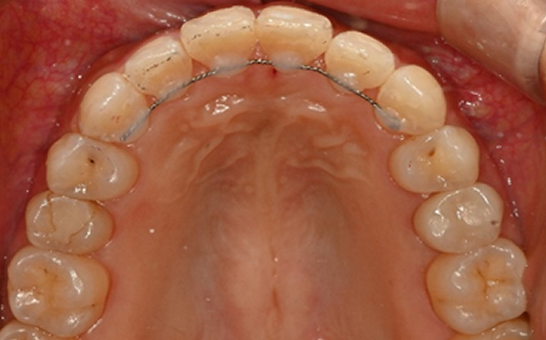

인비절라인(Invisalign)은 눈에 띄지않게 투명하게 제작된 교정 장치입니다.

치아 상태에 맞게 디지털 장비로 맞춤 설계된 투명 교정 장치를 주기적으로 교체하며 치아를 서서히 이동시키는 방식으로 진행됩니다.

기존의 금속 교정 장치와 달리 뛰어난 심미성으로

티나지 않는 교정을 원하시는 경우 적합하며 탈부착이 가능하여 위생관리가 편안합니다.

※ 바른선택치과의원은 의료법을 준수하며 위 케이스는 실제 내원 환자분의 동의하에 공개된 사진과 동일한 환자분께 같은 조건에서 촬영한 사진을 활용했습니다.

개인에 따라 진료 및 치료 방법이 다르게 적용할 수 있으며, 효과와 부작용이 개인마다 다르게 나타날 수 있는 점을 안내해 드리며, 진료 전 전문의료진과 충분한 상담을 권해드립니다.